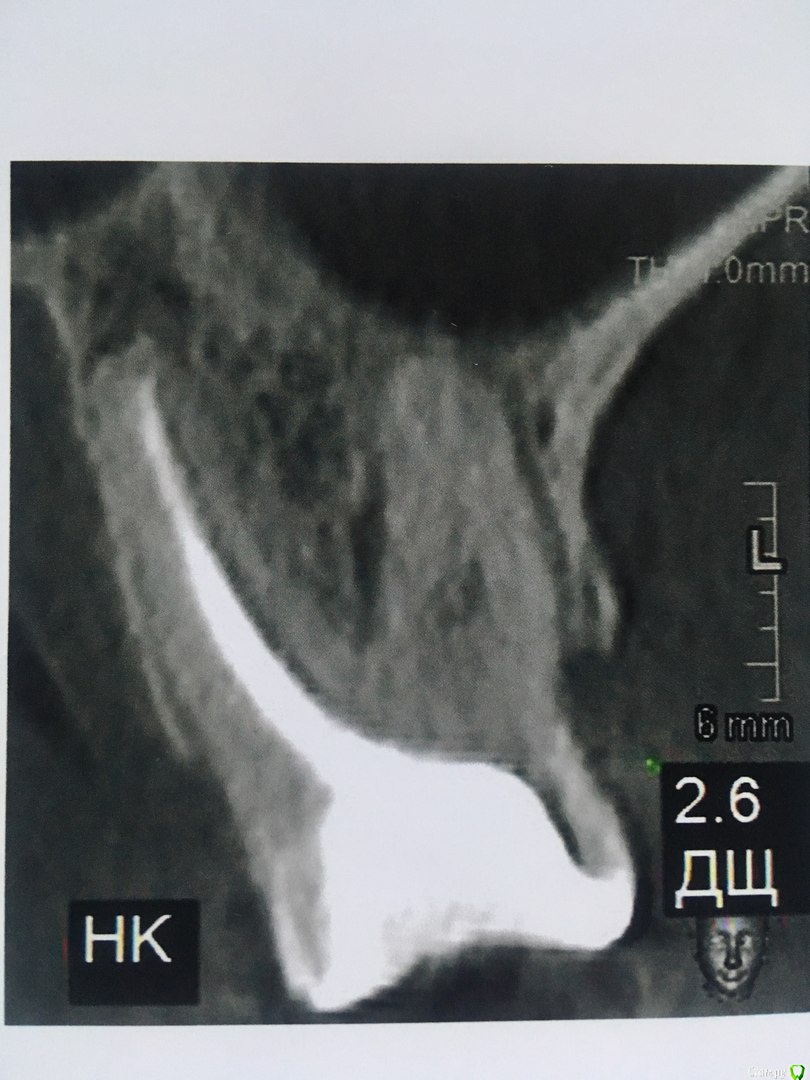

Здравствуйте. Прошу совета у специалистов. Удалять или лечить нижнюю 6-ку?

И вот уже несколько лет нижняя 6-ка периодически ноет (особенно если остыть),каждый год ходила  к одному хирургу,готовясь  уже удалить этот источник неприятных ощущений, но каждый раз врач делая р.снимок говорил все нормально.

Коронковой части у зуба практически нет,только корень, поставлен штиф  и на него пломба в виде коронки зуба.

В течении  года от зуба опустилась десна и там проглядывается прозрачно-черный корень и очень быстро на 5 и 4-ки обазовались черные пятна.  Сделала КТ. Теперь стоит вопрос долгое  лечение или удаление.Врач говорит все будет видно при вскрытии. Если лечение то долгое и без гарантий.   Мне кажется от корня там мало что осталось,судя по цвету и по тому как быстро испортились рядом стоящие зубы. Может проще не лечить,установить имплант?

Правда один врач сказал,что то вроде убыли костной ткани и имплант удержать будет не чем,кроме того сужение верхней челюсти, рецессия десны и стирание в пришеечной области из за прикуса. В заключении кт -пародонтопатия легкой степени тяжести.

Добрый вечер!  Благодарю за ответ. Побывала у другого врача. Мнения разошлись. Второй доктор сказал 4,6  удаляем, а верхний 2,6 лечим.Первый же доктор сказал наоборот. Можно спросить еще Ваше мнение по 2,6 и 2,5 зубам?)